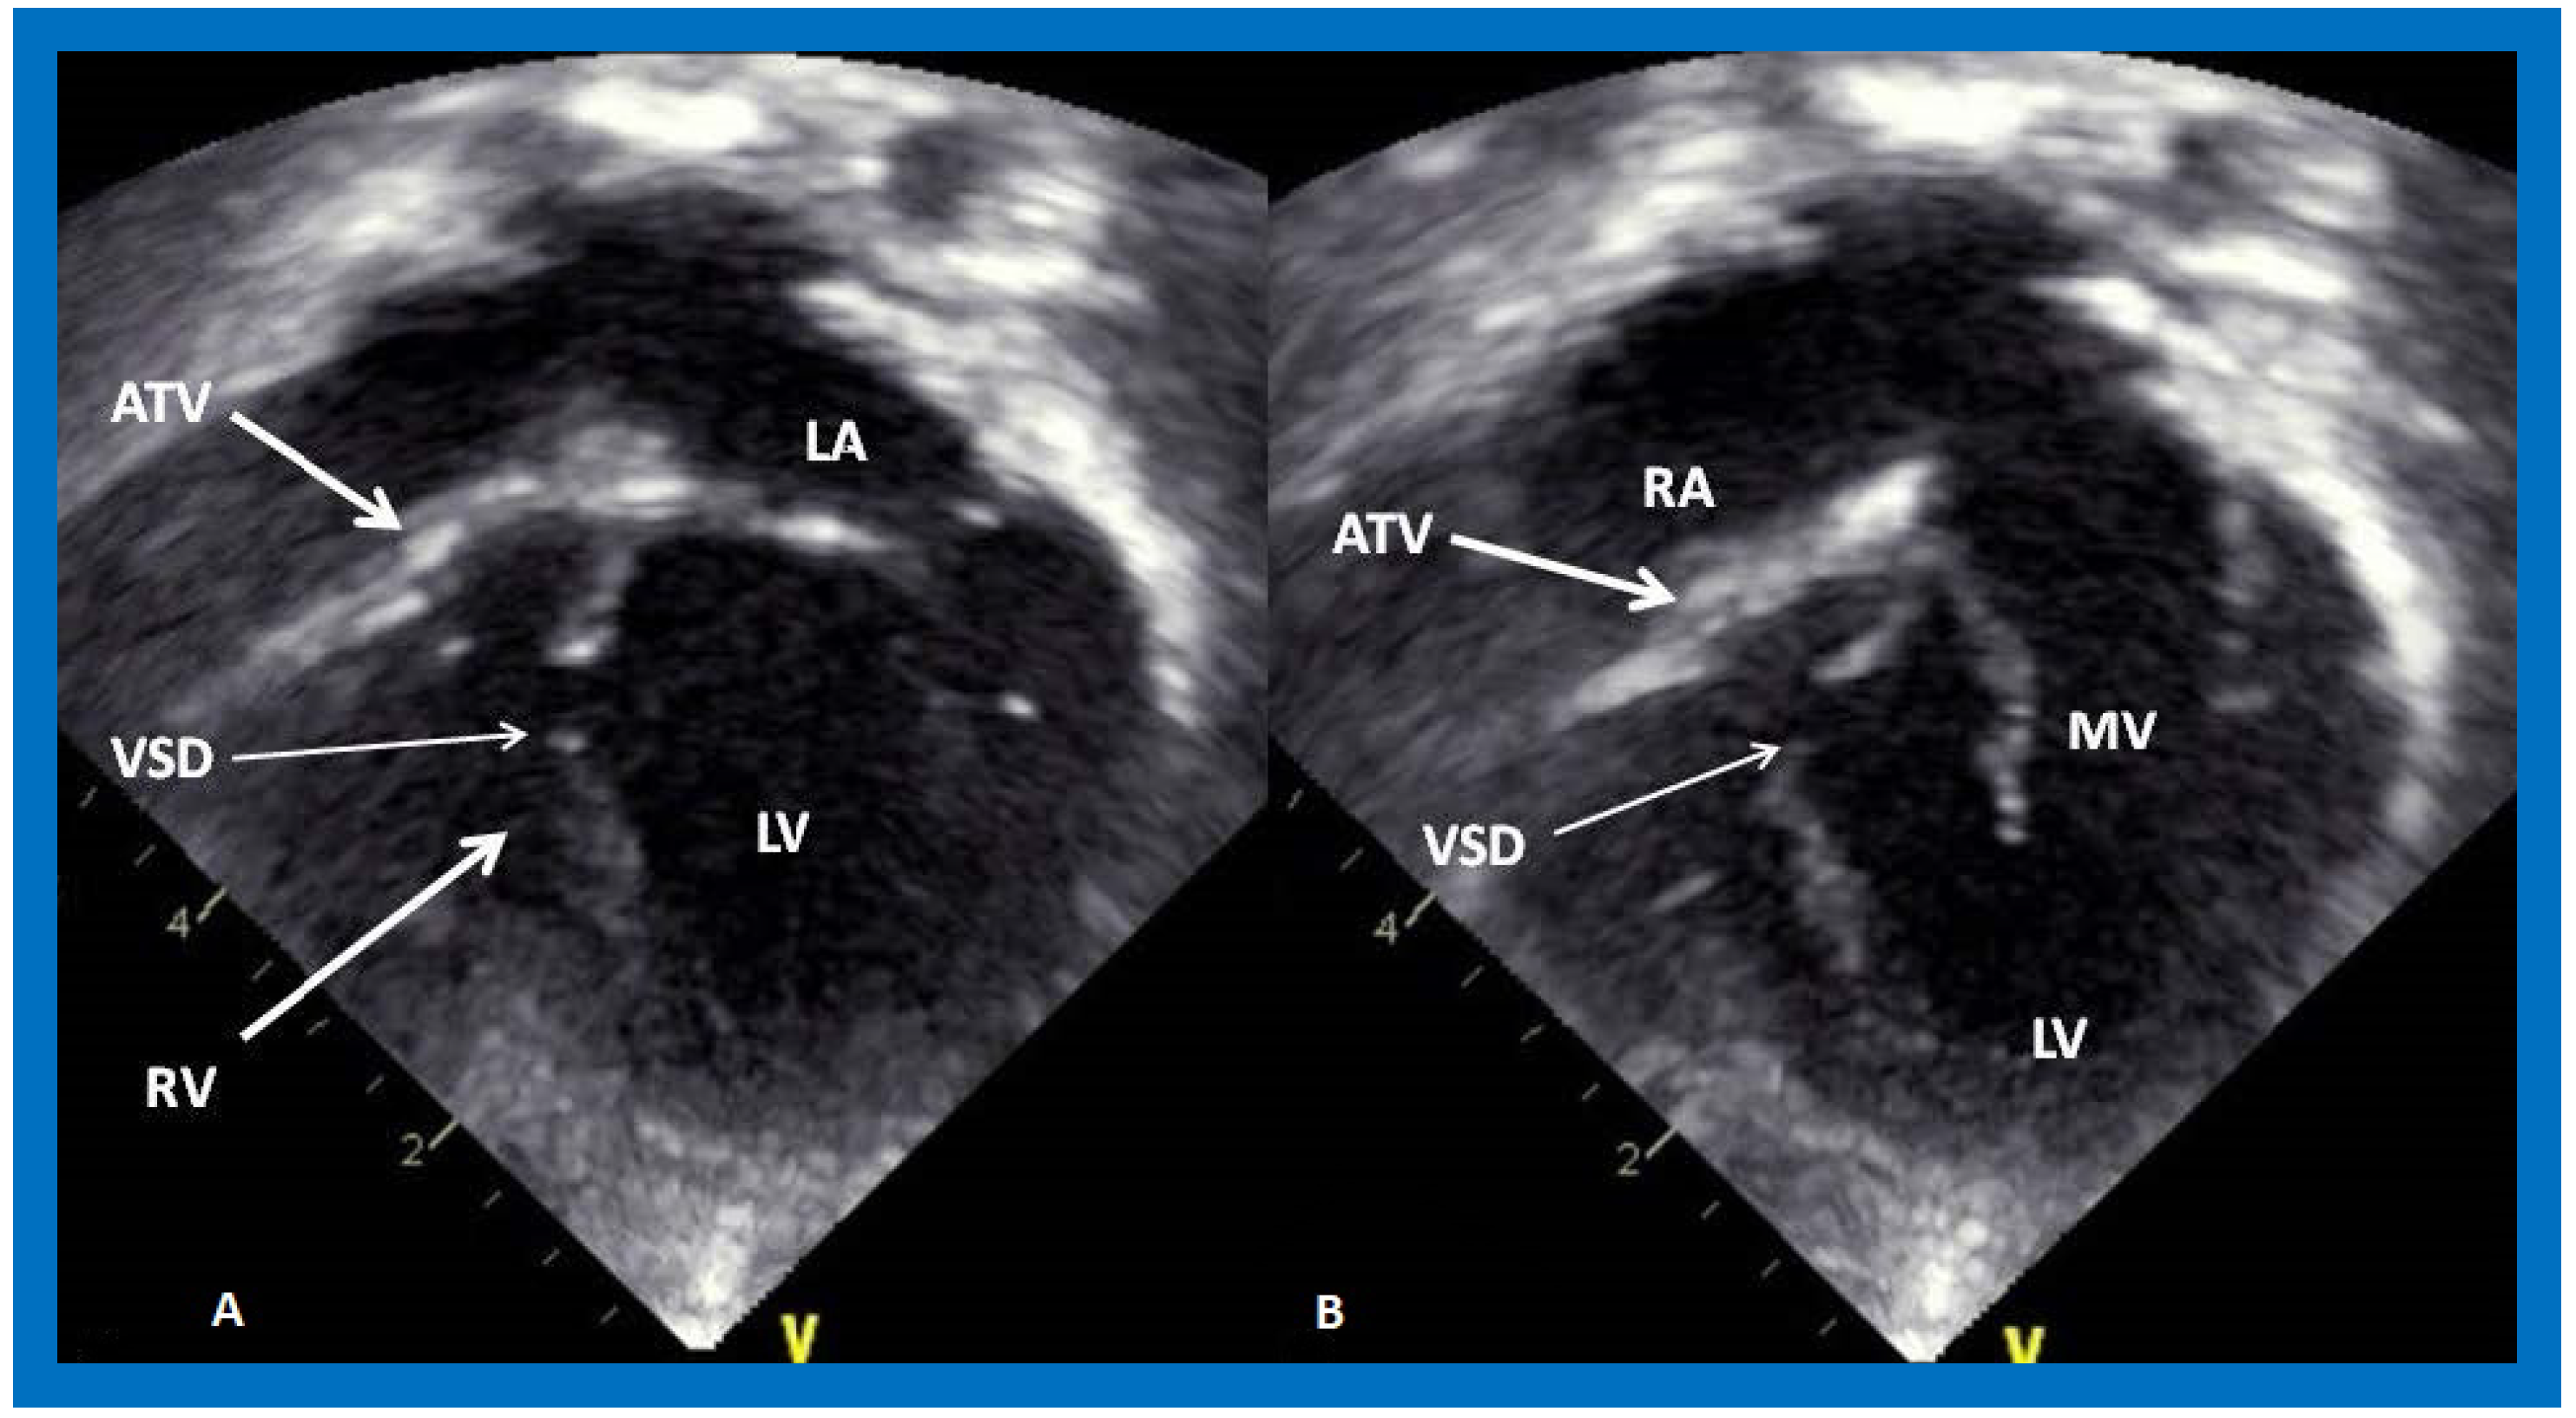

On 2D echocardiography, the atretic tricuspid valve is visualized directly as a dense band of echoes at the site where the tricuspid valve should be, as shown in Figure 4, Figure 5 and Figure 6; this echo appearance is that of the most frequent muscular type of TA. This anatomy is better demonstrated in apical and subcostal four chamber views than in other views. The other anatomic types (Figure 1), namely, membranous, valvular, Ebstein’s, atrioventricular septal defect, and unguarded tricuspid valve with muscular shelf, are rare and may also be recognized on 2D echocardiography. An example of an atrioventricular septal defect type of TA [30] is demonstrated in Figure 7; in this example, a 2D echocardiogram demonstrated an ostium primum ASD with a common atrioventricular valve and a small RV (Figure 7a,b); the entry into the RV appeared to be occluded by a leaflet of the common atrioventricular valve. Left ventricular and right atrial cineangiograms confirmed these findings [30]. Evaluation of the crux cordis (Figure 8) on a 2D echocardiogram (subcostal four chamber view) may help to distinguish the various anatomic types (Figure 1) from each other. In the muscular type of tricuspid atresia, a dense band of echoes is seen where the normal tricuspid valve should be (Figure 8A). In membranous types of tricuspid atresia, a thin membrane is seen instead (Figure 8B). In both these types, the anterior leaflet of the detectable atrioventricular valve is attached to the left side of the interatrial septum (Figure 8A,B). In the atrioventricular septal defect type of tricuspid atresia, the crux cordis is abnormal and cannot be identified; the anterior leaflet of the detectable atrioventricular defect is attached to the anterior wall of the heart, and a large atrioventricular valve leaflet occludes the entry of the RA into the RV (Figure 8C). Based on these observations, it was concluded that 2D echocardiographic (and angiographic) features help to differentiate the atrioventricular canal type of tricuspid atresia from the classic muscular tricuspid atresia cases [30].

Figure 4. Selected video frames from subcostal four chamber view of a two dimensional echocardiographic study demonstrating an atretic tricuspid valve (ATV) (thick arrow), represented by a dense band of echoes between the right atrium (RA) and hypoplastic right ventricle (RV). In (A), the mitral valve (MV) is closed while in (B), it is open. Note the improvement from the pictures shown in Figure 2. LA, left atrium; LV, left ventricle. Reproduced from Reference [27].

Figure 6. Selected video frames from apical four chamber, two dimensional echocardiographic views of a patient with tricuspid atresia showing an enlarged left ventricle (LV), a small right ventricle (RV) and a dense band of echoes at the site where the tricuspid valve echo should be (ATV) (thick arrow) with a closed (A) and open (B) mitral valve. A moderate sized ventricular septal defect (VSD) (thin arrow) is shown. LA, left atrium; RA, right atrium. Reproduced from Reference [29].